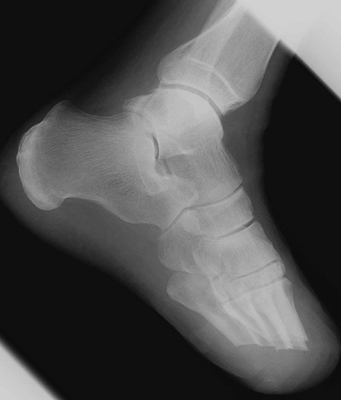

Another transmetatarsal amputation.